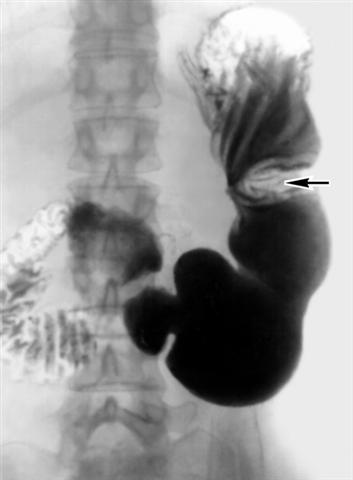

Рис. 3. Рентгенограмма желудка (прямая проекция) при язве малой кривизны: стрелкой указано втяжение контура большой кривизны желудка, обусловленное локальным спазмом.